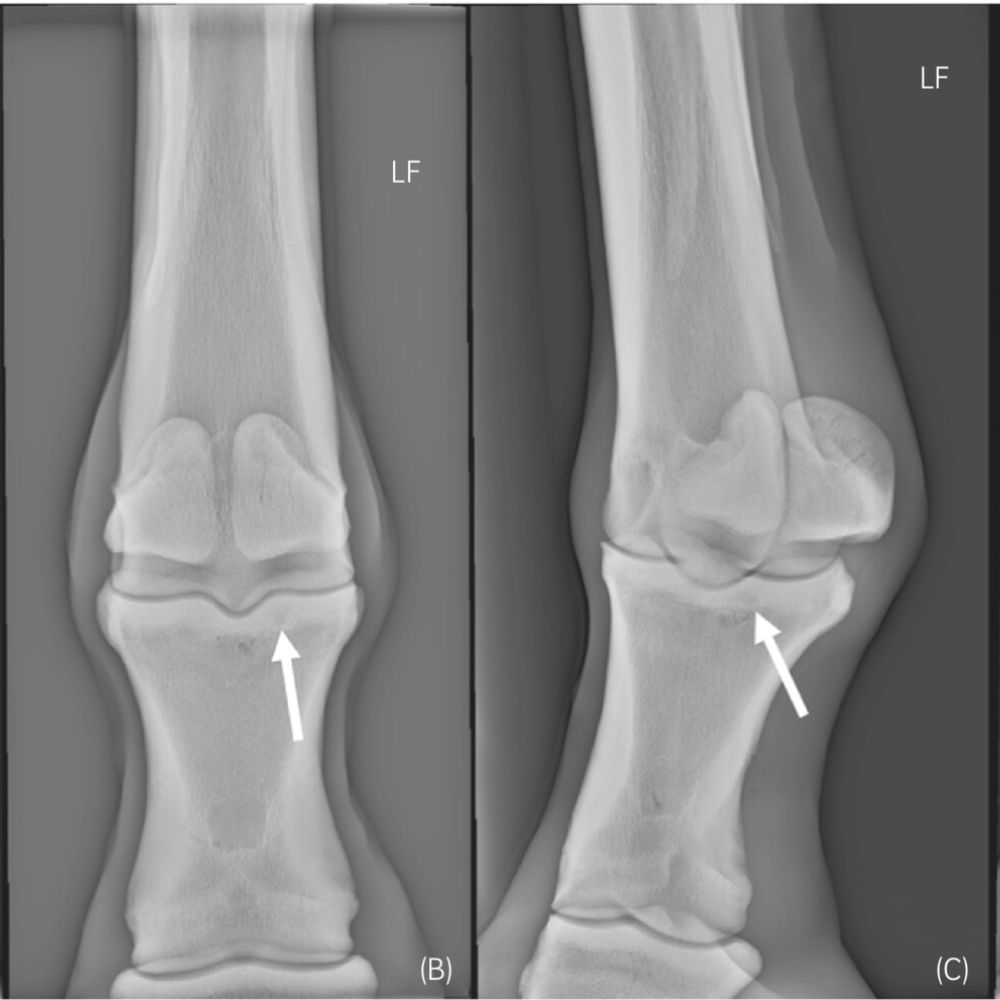

Improve your interpretation of radiographs and ultrasound images, with practical guidance on imaging techniques and common pitfalls.

Radiographic Interpretation of the Foot and Pastern: Common Findings and Misinterpretations |

Radiographic Interpretation of the Neck: What Practitioners Should Look For |